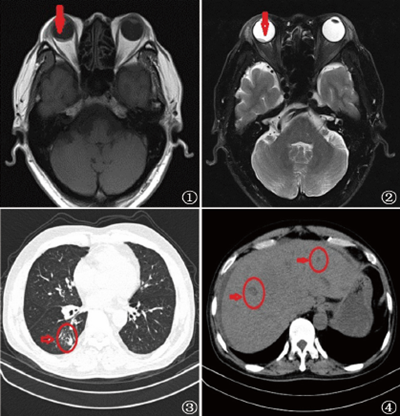

眼科检查:右眼视力0.1,左眼视力1.0,双眼结膜无充血,角膜透明,前房深浅正常,瞳孔圆,对光反射灵敏,晶状体密度稍增高。查右眼眼底后极部视网膜实性隆起,色灰白,视网膜表面可见弯曲爬行的血管,黄斑中心凹反光消失,未见视网膜裂孔,左眼眼底未见明显异常。右眼B型超声检查提示:右眼后极部可见数个不规则低回声隆起区,右眼继发性视网膜合并脉络膜脱离。头颅MRI提示:右眼球壁异常信号,考虑肿瘤合并视网膜脱离(图1,2)。胸腹部CT检查提示:(1)右肺下叶背段肺癌伴右肺门多发淋巴结肿大(图3)。(2)肝内多发转移灶(图4)。血常规检查:C反应蛋白26.6 mg/L;血生化检查:白蛋白 39.8 g/L、氨酸">丙氨酸氨基转移酶234 U/L、天门冬氨酸氨基转移酶44U/L、乳酸脱氢酶344 U/L。

图1,2 MRI示:右眼内肿瘤合并视网膜脱离;图 3 右肺癌伴肺门多发性淋巴结肿大;图 4 肝内多发性转移灶